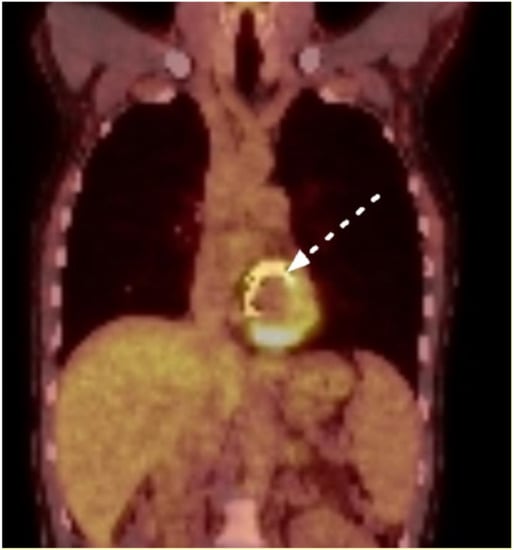

| PET-CT cardiac findings | |

| Strongly positive | 3 (43) |

| Slightly positive | 1 (14) |

| Unremarkable | 2 (28) |